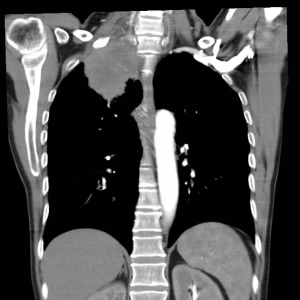

| DISPNEEA – 45% dintre pacienți | |

| Oboseala poate fi determinată de prezența unei formațiuni tumorale care obstruează căile aeriene, prezența de lichid în spațiul pleural (revărsat pleural) sau în pericard (foița care acoperă inima) purtând denumirea de pericardită, prezența a numeroși micronoduli și noduli distribuiți aleatori în ambele campuri pulmonare care ar putea să ridice suspiciunea unei carcinomatoze pulmonare și nu în ultimul rând prezența unei pneumonii retrostenotice sau atelectazii [căile respiratorii sau saculeții cu aer (alveolele) nu se mai pot dilata]. Pentru evaluarea dispneei se utilizeză scala Borg și mMRC. | |

- Simptome date de diseminarea intratoracică: revărsat pleural, revărsat pericardic, chilotorax (prezența de lichid pleural ca urmare a unei obstrucții la nivelul canalului limfatic), disfonie (compresiunea/invazia nervului laringeu recurent), disfagie (compresiunea/invazia esofagului), sindrom de venă cavă superioară (cefalee, edem în pelerină, venectazii și cianoză), sindromul Claude – Bernard – Horner (ptoza palpebrală, enoftalmie, mioză) și tumora Pancoast – Tobias (prezența unei formațiuni tumorale care erodează arcul costal și invadează plexul brahial de aceeași parte – homolateral, cu apariția unui sindrom algic și atrofierea musculaturii membrului superior).